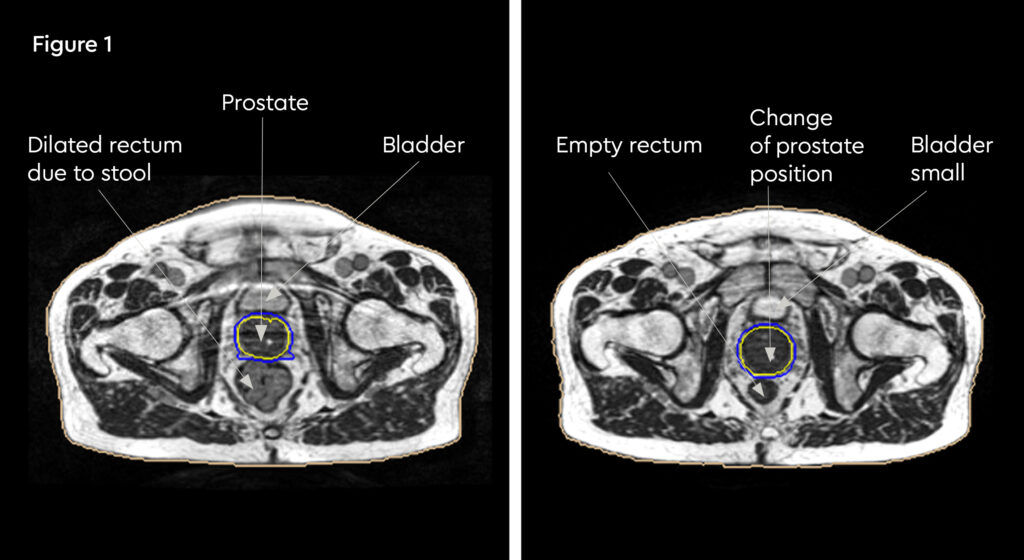

At each session, daily adaptation was performed to account for changes in the position of the prostate and for variable bladder and bowel filling. Figure 1 and figure 2 illustrate the typical differences seen between the original planning MRIdian scan and that seen on the day of treatment due to day-to-day organ movement. Figure 3 and figure 4 illustrate how these movements were accommodated with the on-table plan adaptation.

Fig 1: Original planning MRIdian scan

Fig 2: MRIdian scan at fraction 3, prostate position changed due to larger rectal diameter secondary to gas and smaller bladder